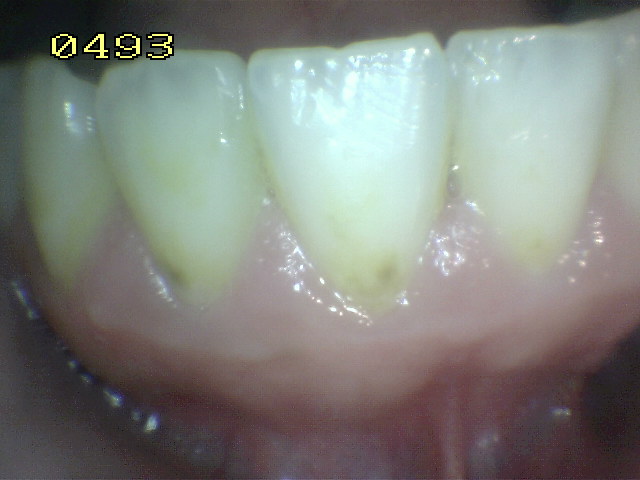

- Remueva las manchas superficiales y el cálculo dental de las

superficies dentarias